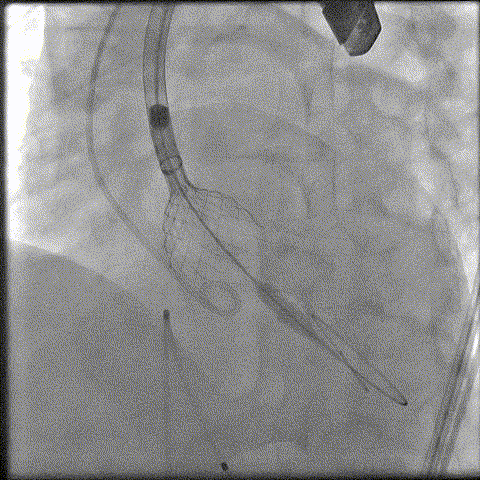

预扩

猪尾中部释放

稳定回收

评估

最终释放

后扩

无瓣周漏